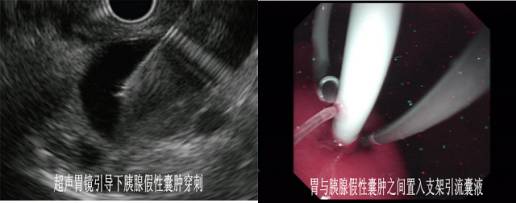

EUS-FNA的适应症:1)用于胃肠道及其邻近组织(含淋巴结)病灶的细胞学和组织学诊断。2)纵膈病变、胰腺病变、胆管及肝脏病变、胃肠道粘膜下肿瘤。

3)超声内镜引导下胰腺假性囊肿胃置管引流术。